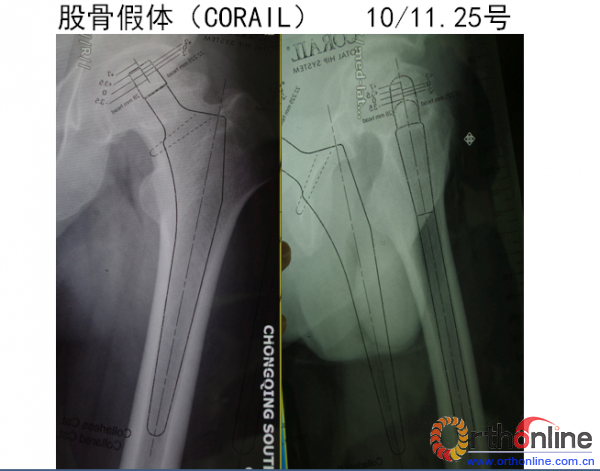

讨论点:Corail 柄在骨质较好的患者中的应用,为什么模板测量通常大于实际选择假体? 如何选择陶瓷股骨头?标准头好还是减头好?肢体长度如何均衡?Corail 柄下沉技术?髋臼磨锉技巧? pinnacle常规需要螺钉固定吗?

麻醉方式:腰硬联合 体位:右侧卧位 手术方式:左侧人工全髋关节置换术 使用假体:髋臼:PINNACLE 股骨柄:CORAIL 入路:后外侧MIS切口